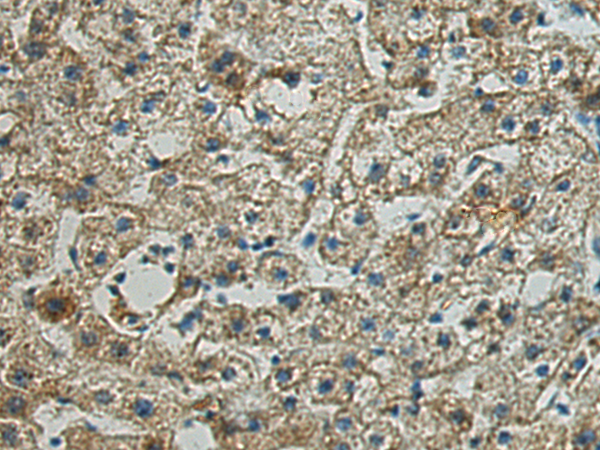

分类: 科研抗体货号: P00278别名: HML; MGL; HML2; CD301; CLECSF13; CLECSF14应用: WB,IHC反应种属: Human